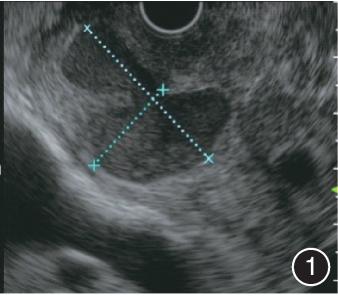

患者男,50岁,因“间断性上腹部疼痛5个月余”入院。入院前胰腺MRI平扫及动态增强扫描提示:胰头与十二指肠间可见不规则稍低T1信号以及稍高T2信号,局部可见分层,DWI呈不均匀稍高信号,并可见囊状无强化区。超声内镜检查提示:胰头钩突与十二指肠肠壁之间可见一囊性病变(图1)。结合患者的胰腺MRI和超声内镜检查结果,考虑诊断为沟槽状胰腺炎合并假性囊肿。

图1 入院前超声内镜检查提示胰头钩突与十二指肠肠壁之间可见一囊性病变